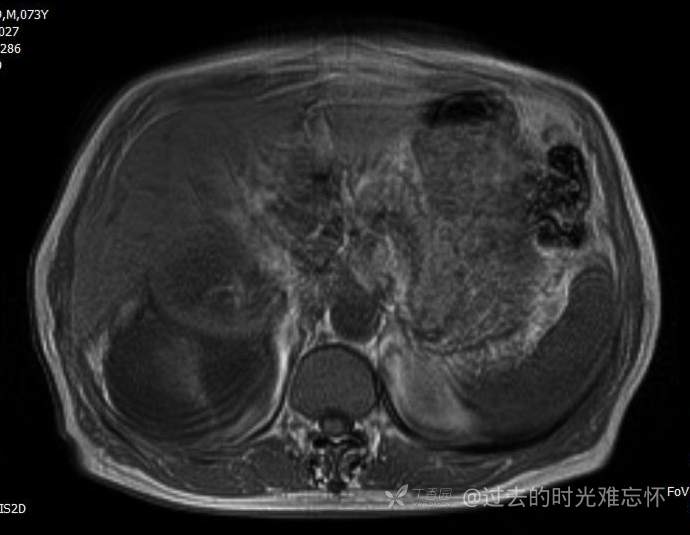

患者性别:男

患者年龄:73岁

主诉:咳嗽1月余。曾有血尿一次。后背部酸痛不适1-2年左右,无明显消瘦。

辅助检查:CT MRI

临床诊断:占位

治疗经过:手术

T1 及 T1压脂

T2压脂